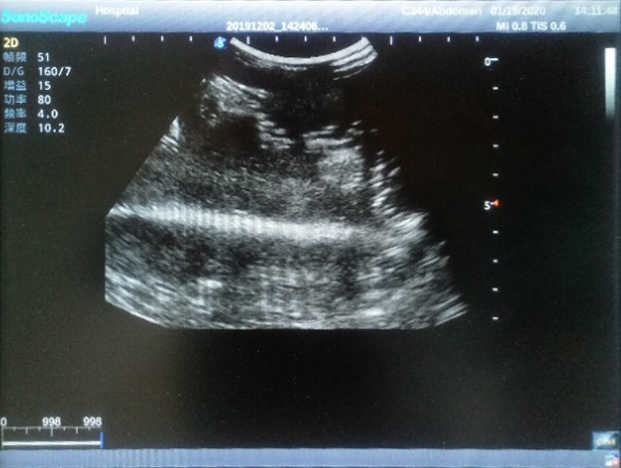

Wearable Breast Ultrasound Examination Model

Model TYE1568.1

The Wearable Breast Ultrasound Examination Model allows users to develop and practice the skills necessary to gain proficiency in breast palpation, using ultrasound for normal and abnormal imaging and biopsy. It simulates adult female breasts with realistic size and appearance.

2)  Each model contains 8 space-occupying lesions of varying sizes, different in touch, elasticity and ultrasonogram

4) Biomimetic material allowing users to see clear and real normal tissues and space-occupying lesions that are hyperechoic, hypoechoic and isoechoic as they would see in the clinical environment